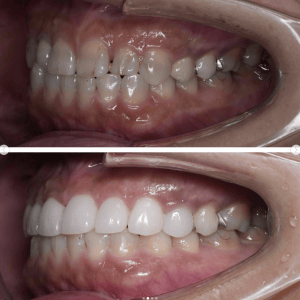

Case006 – ワイヤー矯正

片顎抜歯を行い、主に上の前歯の歯並びを矯正した症例です。